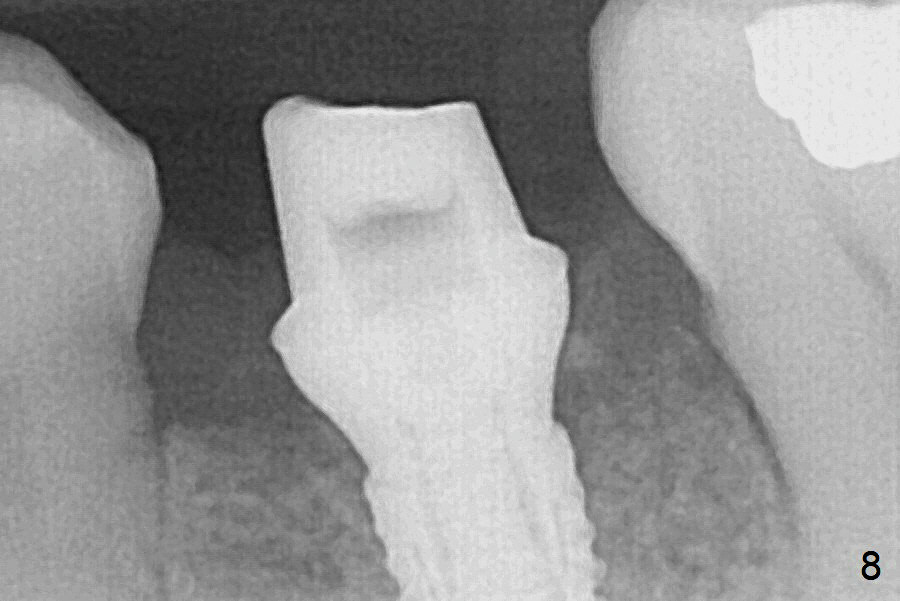

Extraction of the lower left 2nd premolar with vertical fracture (Fig.1,2 >) is easy because of peri-radicular radiolucency.  The apical end of the osteotomy is not shown with a 2 mm pilot drill (Fig.3) or a 3.8x18 mm implant (Fig.4) in place.  It appears that the implant is not placed deep enough.  Following 3-4 more turns of the implant and placement of a 5.5x4(3) mm abutment (Fig.5 A), allograft is placed (*).  A postop panoramic X-ray is taken (Fig.6); the osteotomy could have been deepened to reduce the possibility of periimplantitis.  Retrospectively, the panoramic X-ray should be taken after use of the pilot drill. The bone around the implant appears to have regenerated 4 months postop (Fig.7,8).  Bone density appears to continue increasing 9 months postop (i.e., 4.5 months post cementation, Fig.9).  Bone loss is minimal 2 years post cementation (Fig.10).